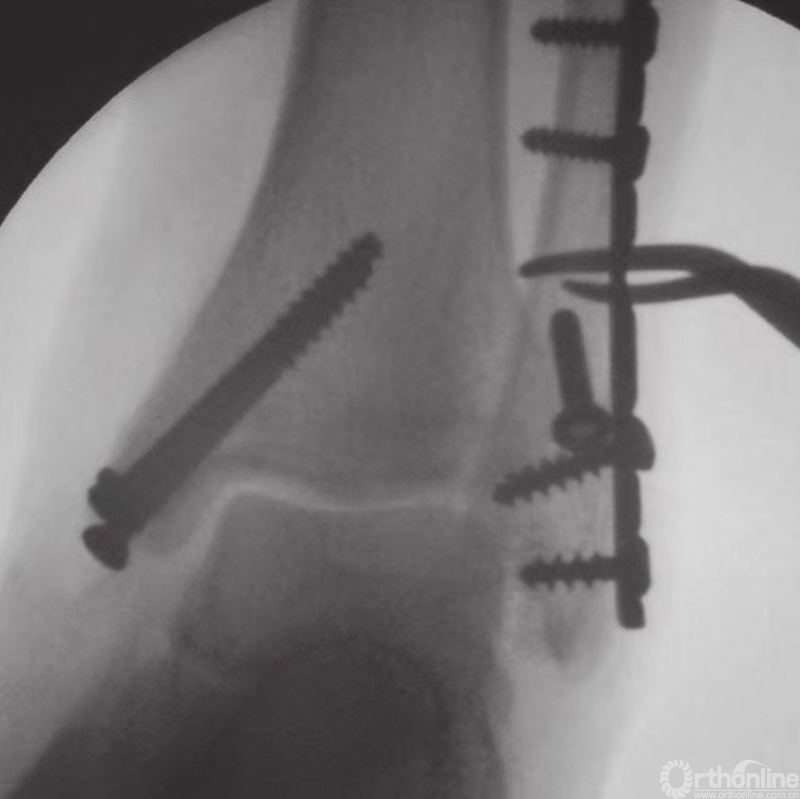

通过X线透视确认骨折复位和螺钉的固定(图19)。用可吸收缝线缝合较薄的皮下层后,再将皮肤缝合。

图19 通过X线透视确认骨折复位和螺钉的固定